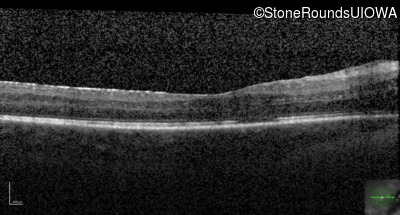

Optical Coherence Tomography - Right - 20/125 -2 sc

Exemplar / OCT Stack

OCT Stack

Optical Coherence Tomography - Left - 20/200 +2 sc